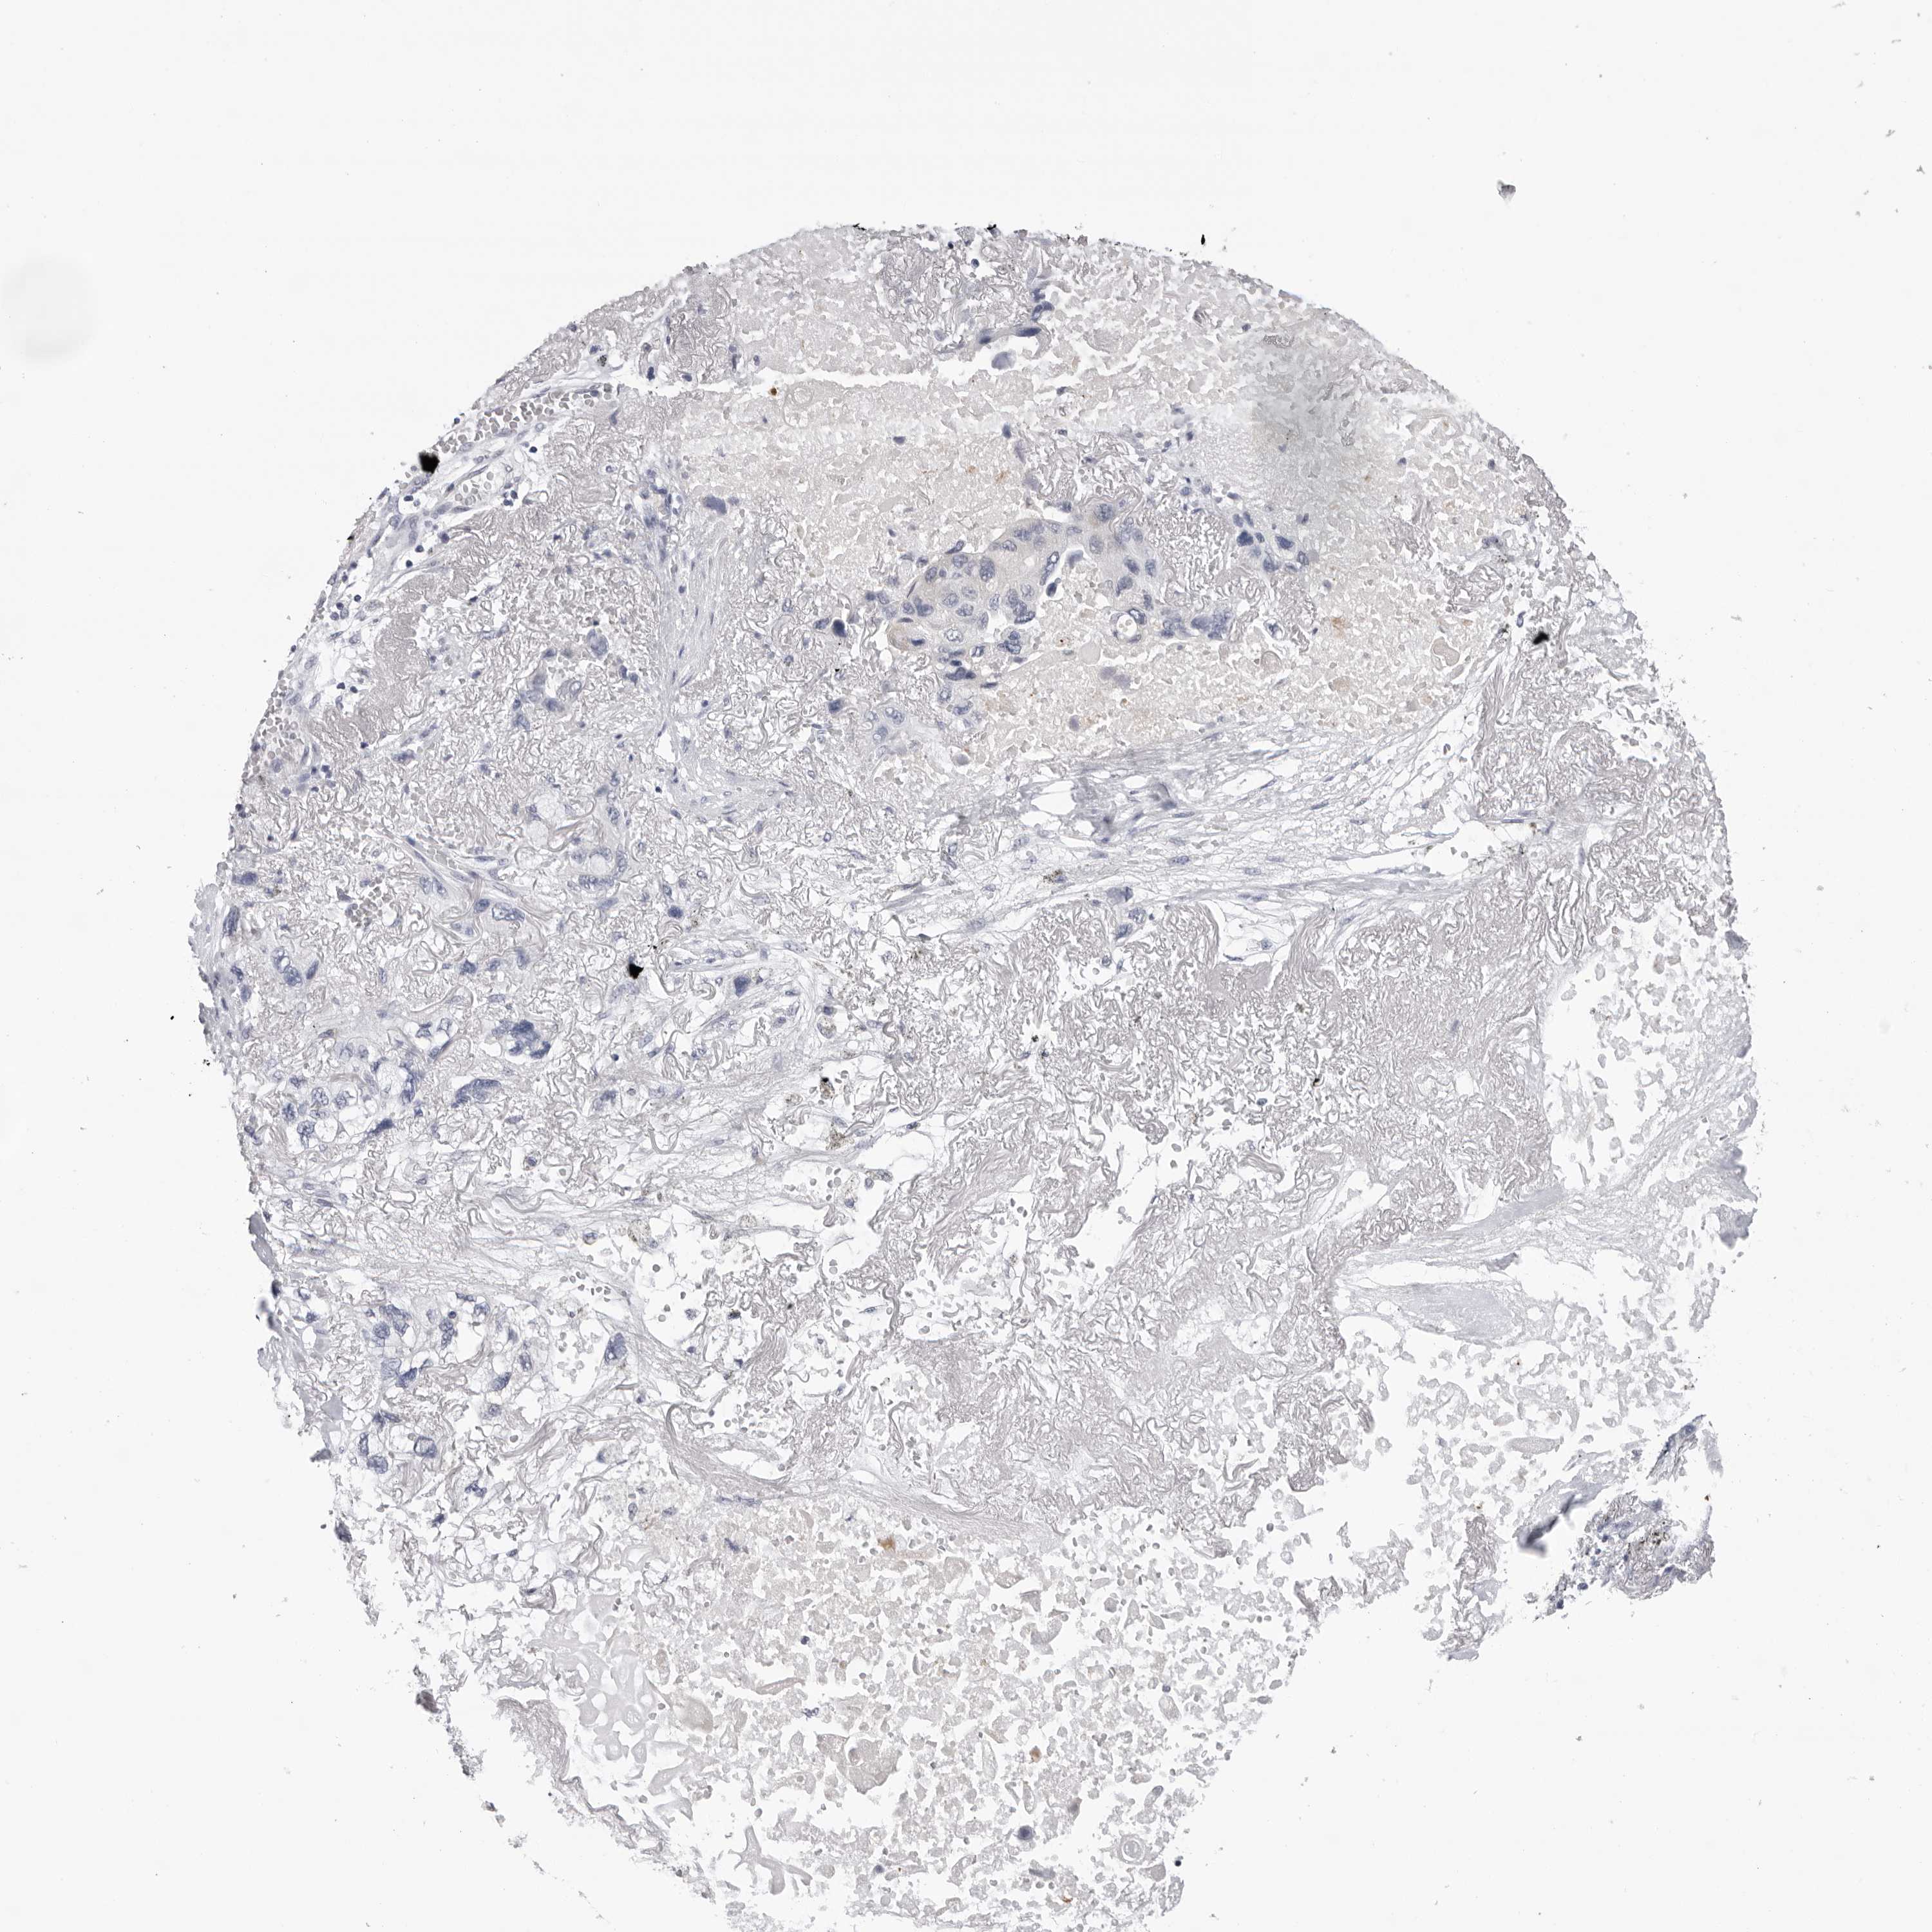

LUNG ADENOCARCINOMA (VALIDATION) - Interactive survival scatter ploti

The Survival Scatter plot shows the clinical status (i.e. dead or alive) for all individuals in the patient cohort, based on the same data that underlies the corresponding Kaplan-Meier plots. Patients that are alive at last time for follow-up are shown in blue and patients who have died during the study are shown in red.

The x-axis shows the expression levels (FPKM) of the investigated gene in the tumor tissue at the time of diagnosis. The y-axis shows the follow-up time after diagnosis (years). Both axes are complimented with kernel density curves demonstrating the data density over the axes. The top density plot shows the expression levels (FPKM) distribution among dead (red) and alive patients (blue). The right density plot shows the data density of the survived years of dead patients with high and low expression levels respectively, stratified using the cutoff indicated by the vertical dashed line through the Survival Scatter plot. This cutoff is automatically defined based on the FPKM cutoff that minimizes the p-score. The cutoff can be changed by dragging the vertical line or by entering a cutoff value in the square labeled "Current cut-off".

Under the Survival Scatter plot the p-score landscape (black curve; left axis) is shown together with dead median separation (red curve; right axis). Dead median separation is the difference in median mRNA expression between patients who have died with high and low expression, respectively. It is calculated as follows: median FPKM expression of dead patients with high expression - median FPKM expression of dead patients with low expression. This is intended to aid the user in visually exploring custom cutoffs and the associated p-scores and dead median separation.

Individual patient data is displayed and can be filtered by clicking on one or more of the category buttons on the top of the page. Categories describing expression level and patient information include: high, low, alive, dead, female, male and tumor stages. The scale of the x-axis can be toggled between linear and log-scale by clicking on the "x log" button. Mouse-over function shows TCGA ID, patient information and mRNA expression (FPKM) for each patient.

& Survival analysisi

Kaplan-Meier plots summarize results from analysis of correlation between mRNA expression level and patient survival. Patients were divided based on level of expression into one of the two groups "low" (under cut off) or "high" (over cut off). X-axis shows time for survival (years) and y-axis shows the probability of survival, where 1.0 corresponds to 100 percent.

ZNF502 is not prognostic in Lung Adenocarcinoma (validation)

Best expression cut offi

Based on the FPKM value of each gene, patients were classified into two groups and association between prognosis (survival) and gene expression (FPKM) was examined. The best expression cut-off refers the FPKM value that yields maximal difference with regard to survival between the two groups at the lowest log-rank P-value. Best expression cut-off was selected based on survival analysis .

When clicking on this number, the vertical dashed line indicating cut-off, the interactive survival plot, and the Kaplan-Meier curve will be adjusted to show results based on the best expression cut-off.

: 1.48

P scorei

Log-rank P value for Kaplan-Meier plot showing results from analysis of correlation between mRNA expression level and patient survival.

N/A

TCGA RNA samplesi

RNA-seq data is reported as average FPKM (number Fragments Per Kilobase of exon per Million reads), generated by the The Cancer Genome Atlas (TCGA) .

Normal distribution across the dataset is visualized with box plots, shown as median and 25th and 75th percentiles. Points are displayed as outliers if they are above or below 1.5 times the interquartile range. FPKM values of the individual samples are presented next to the box plot.

Average pTPM 1.9

Number of samples 105